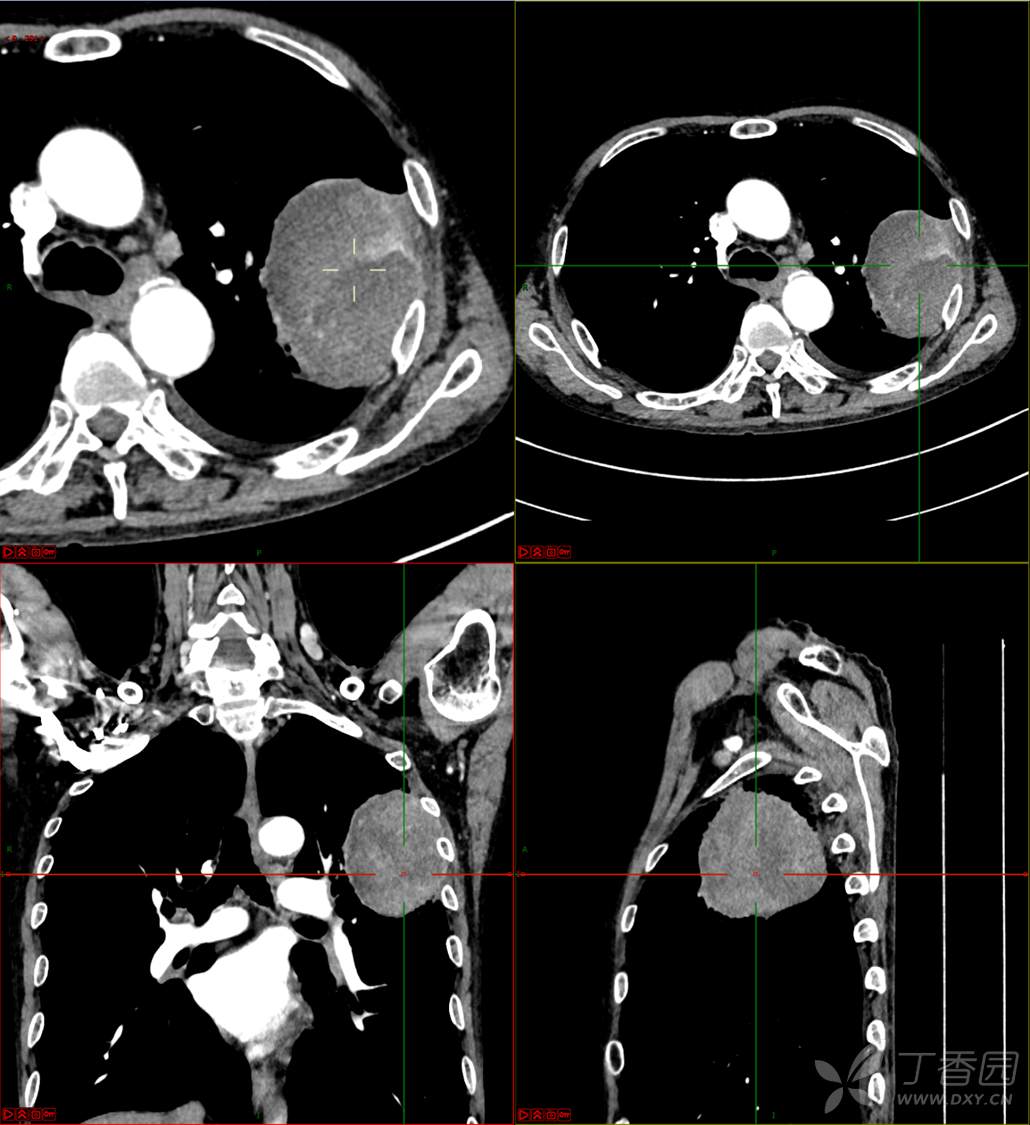

现病史:患者自诉5月前无明显原因及诱因出现纳差、乏力,伴进食后腹胀,无腹痛、腹泻、发热、盗汗、恶心、胸闷,未行特殊处理。1月前无明显原因诱因出现咳嗽,呈阵发性,咳白痰,痰中带鲜红色血丝,10余口/日,无血块,仍伴纳差、乏力、进食后腹胀,无恶心、呕吐、呕血,无头晕、心慌、喘憋、胸闷。在家未行特殊治疗,来我院就诊,2022.8.18行胸部(肺)CT平扫:左上肺占位并左侧肋骨骨质破坏,考虑间叶源性恶性肿瘤。门诊以“肺肿物”收入我科。患者自发病以来,神志清,精神可,饮食差,睡眠可,二便正常,近3月减轻5Kg。